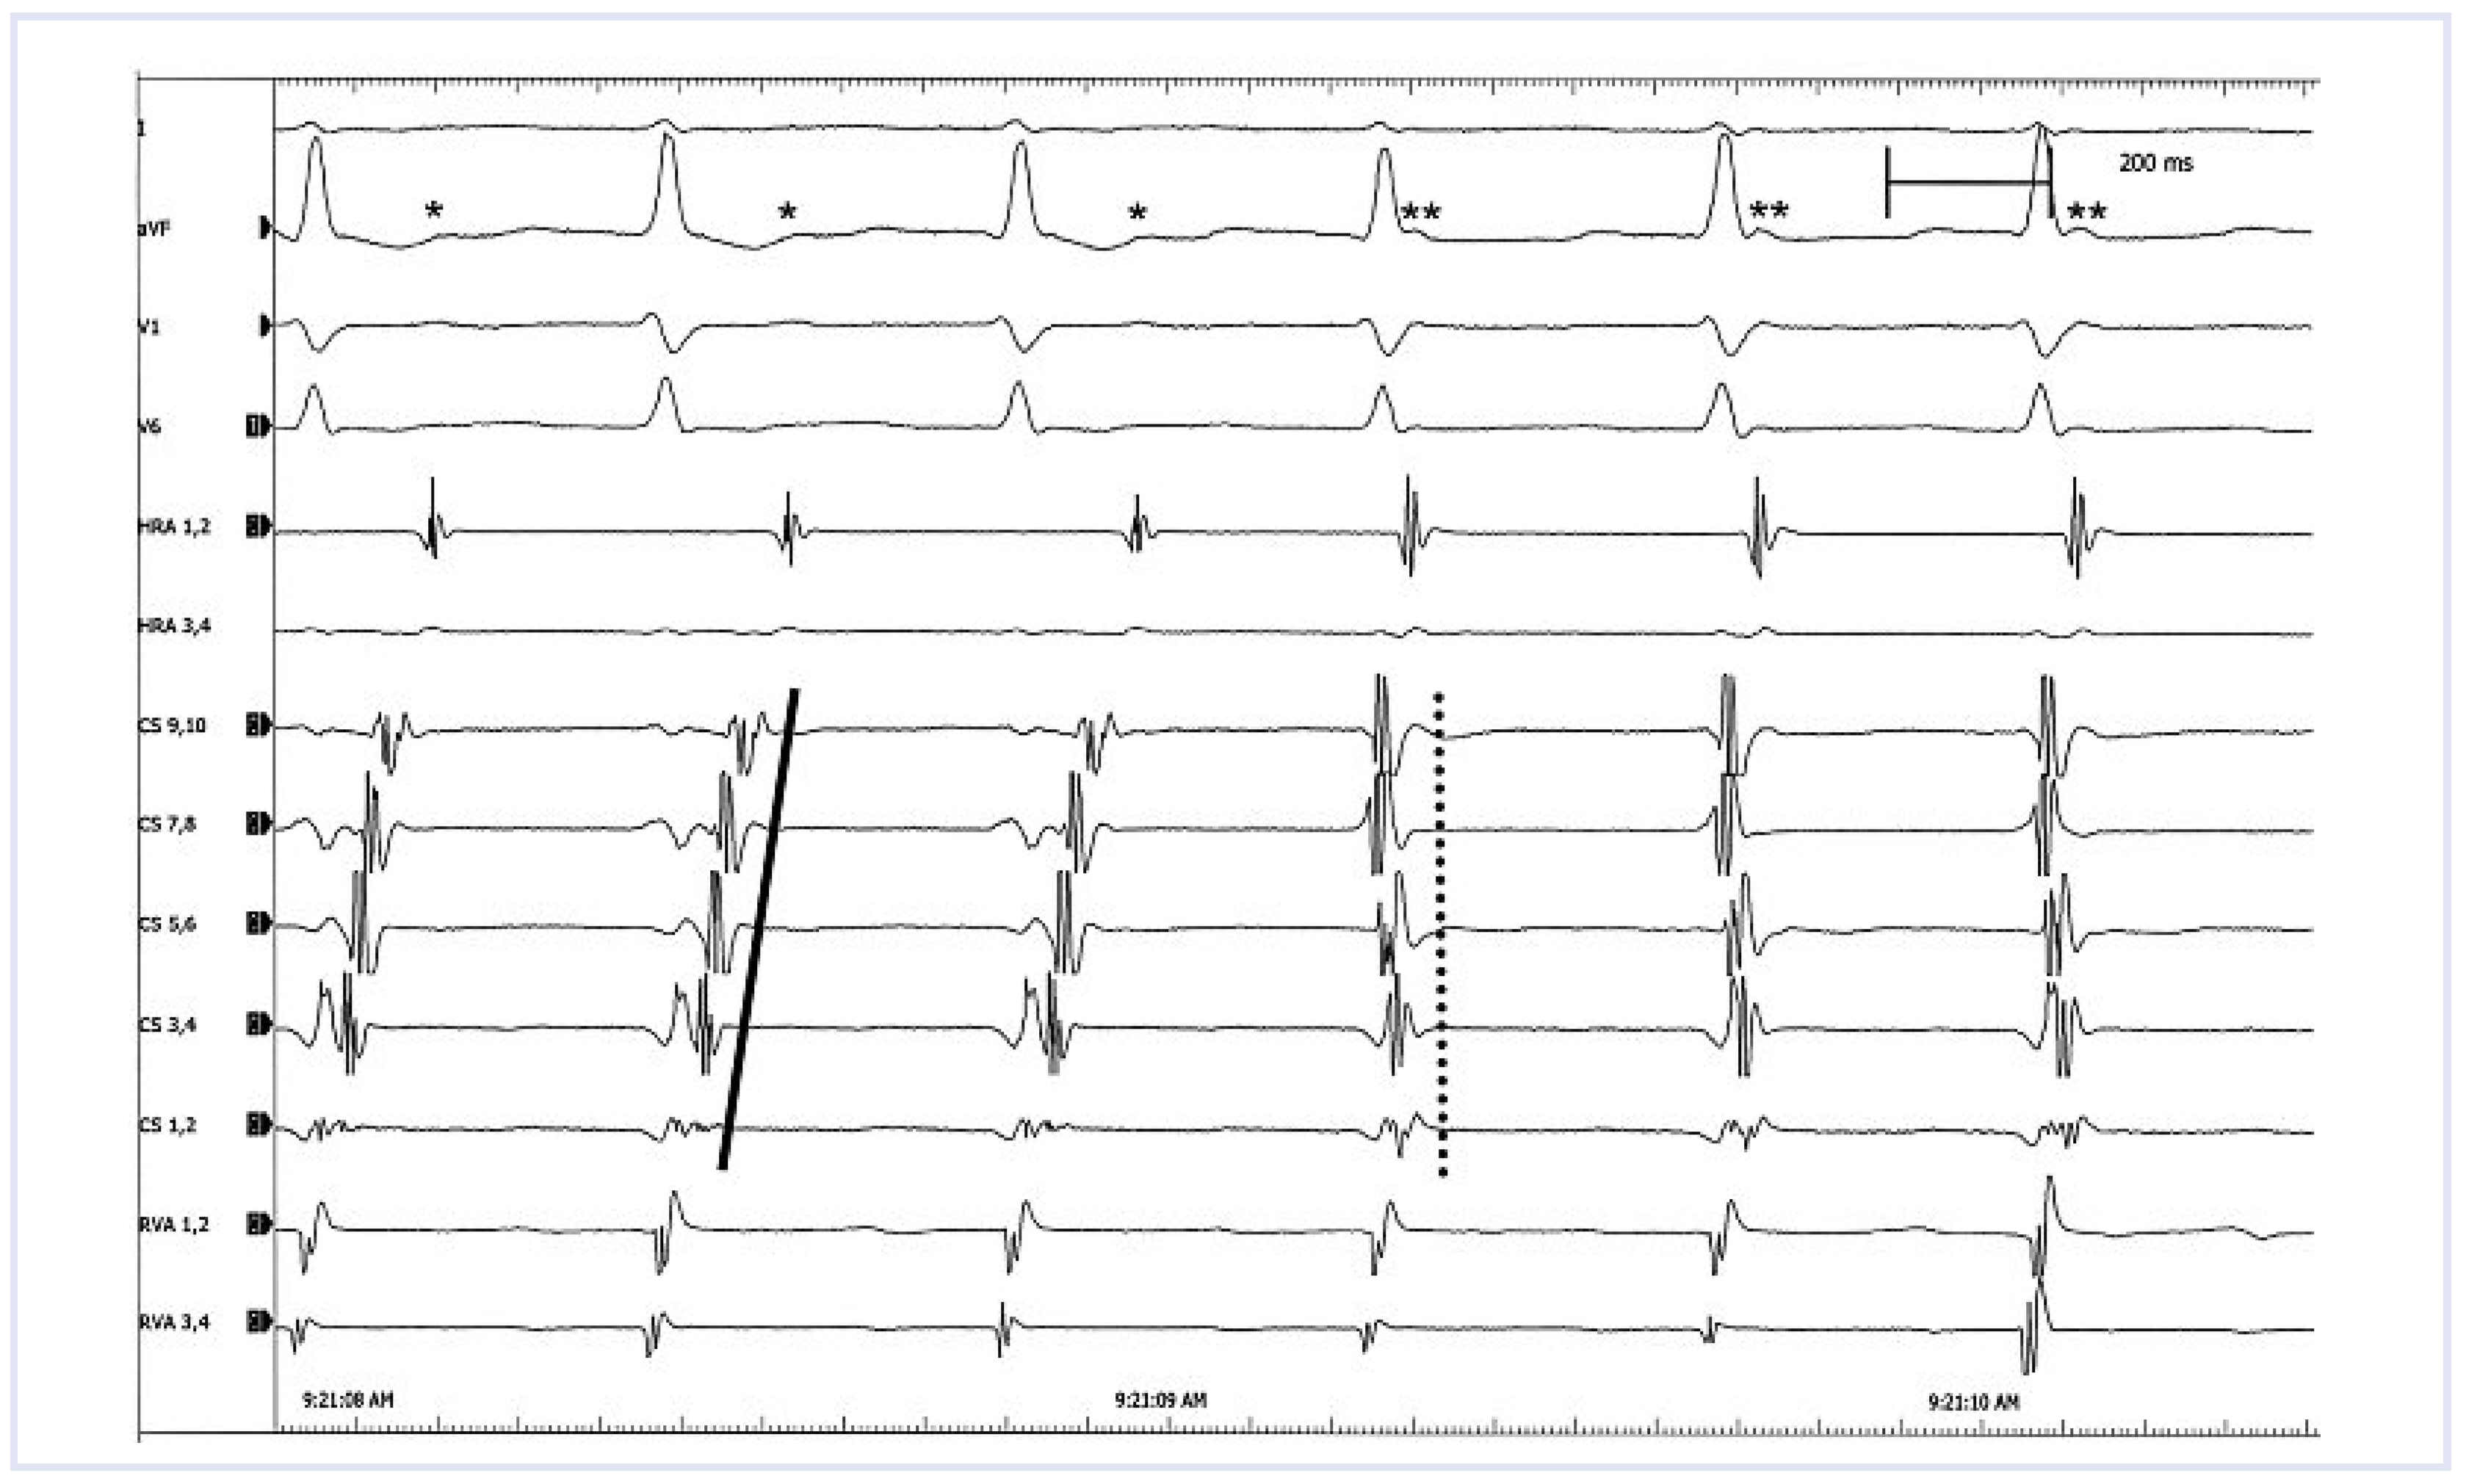

Just a Supraventricular Tachycardia

Case report